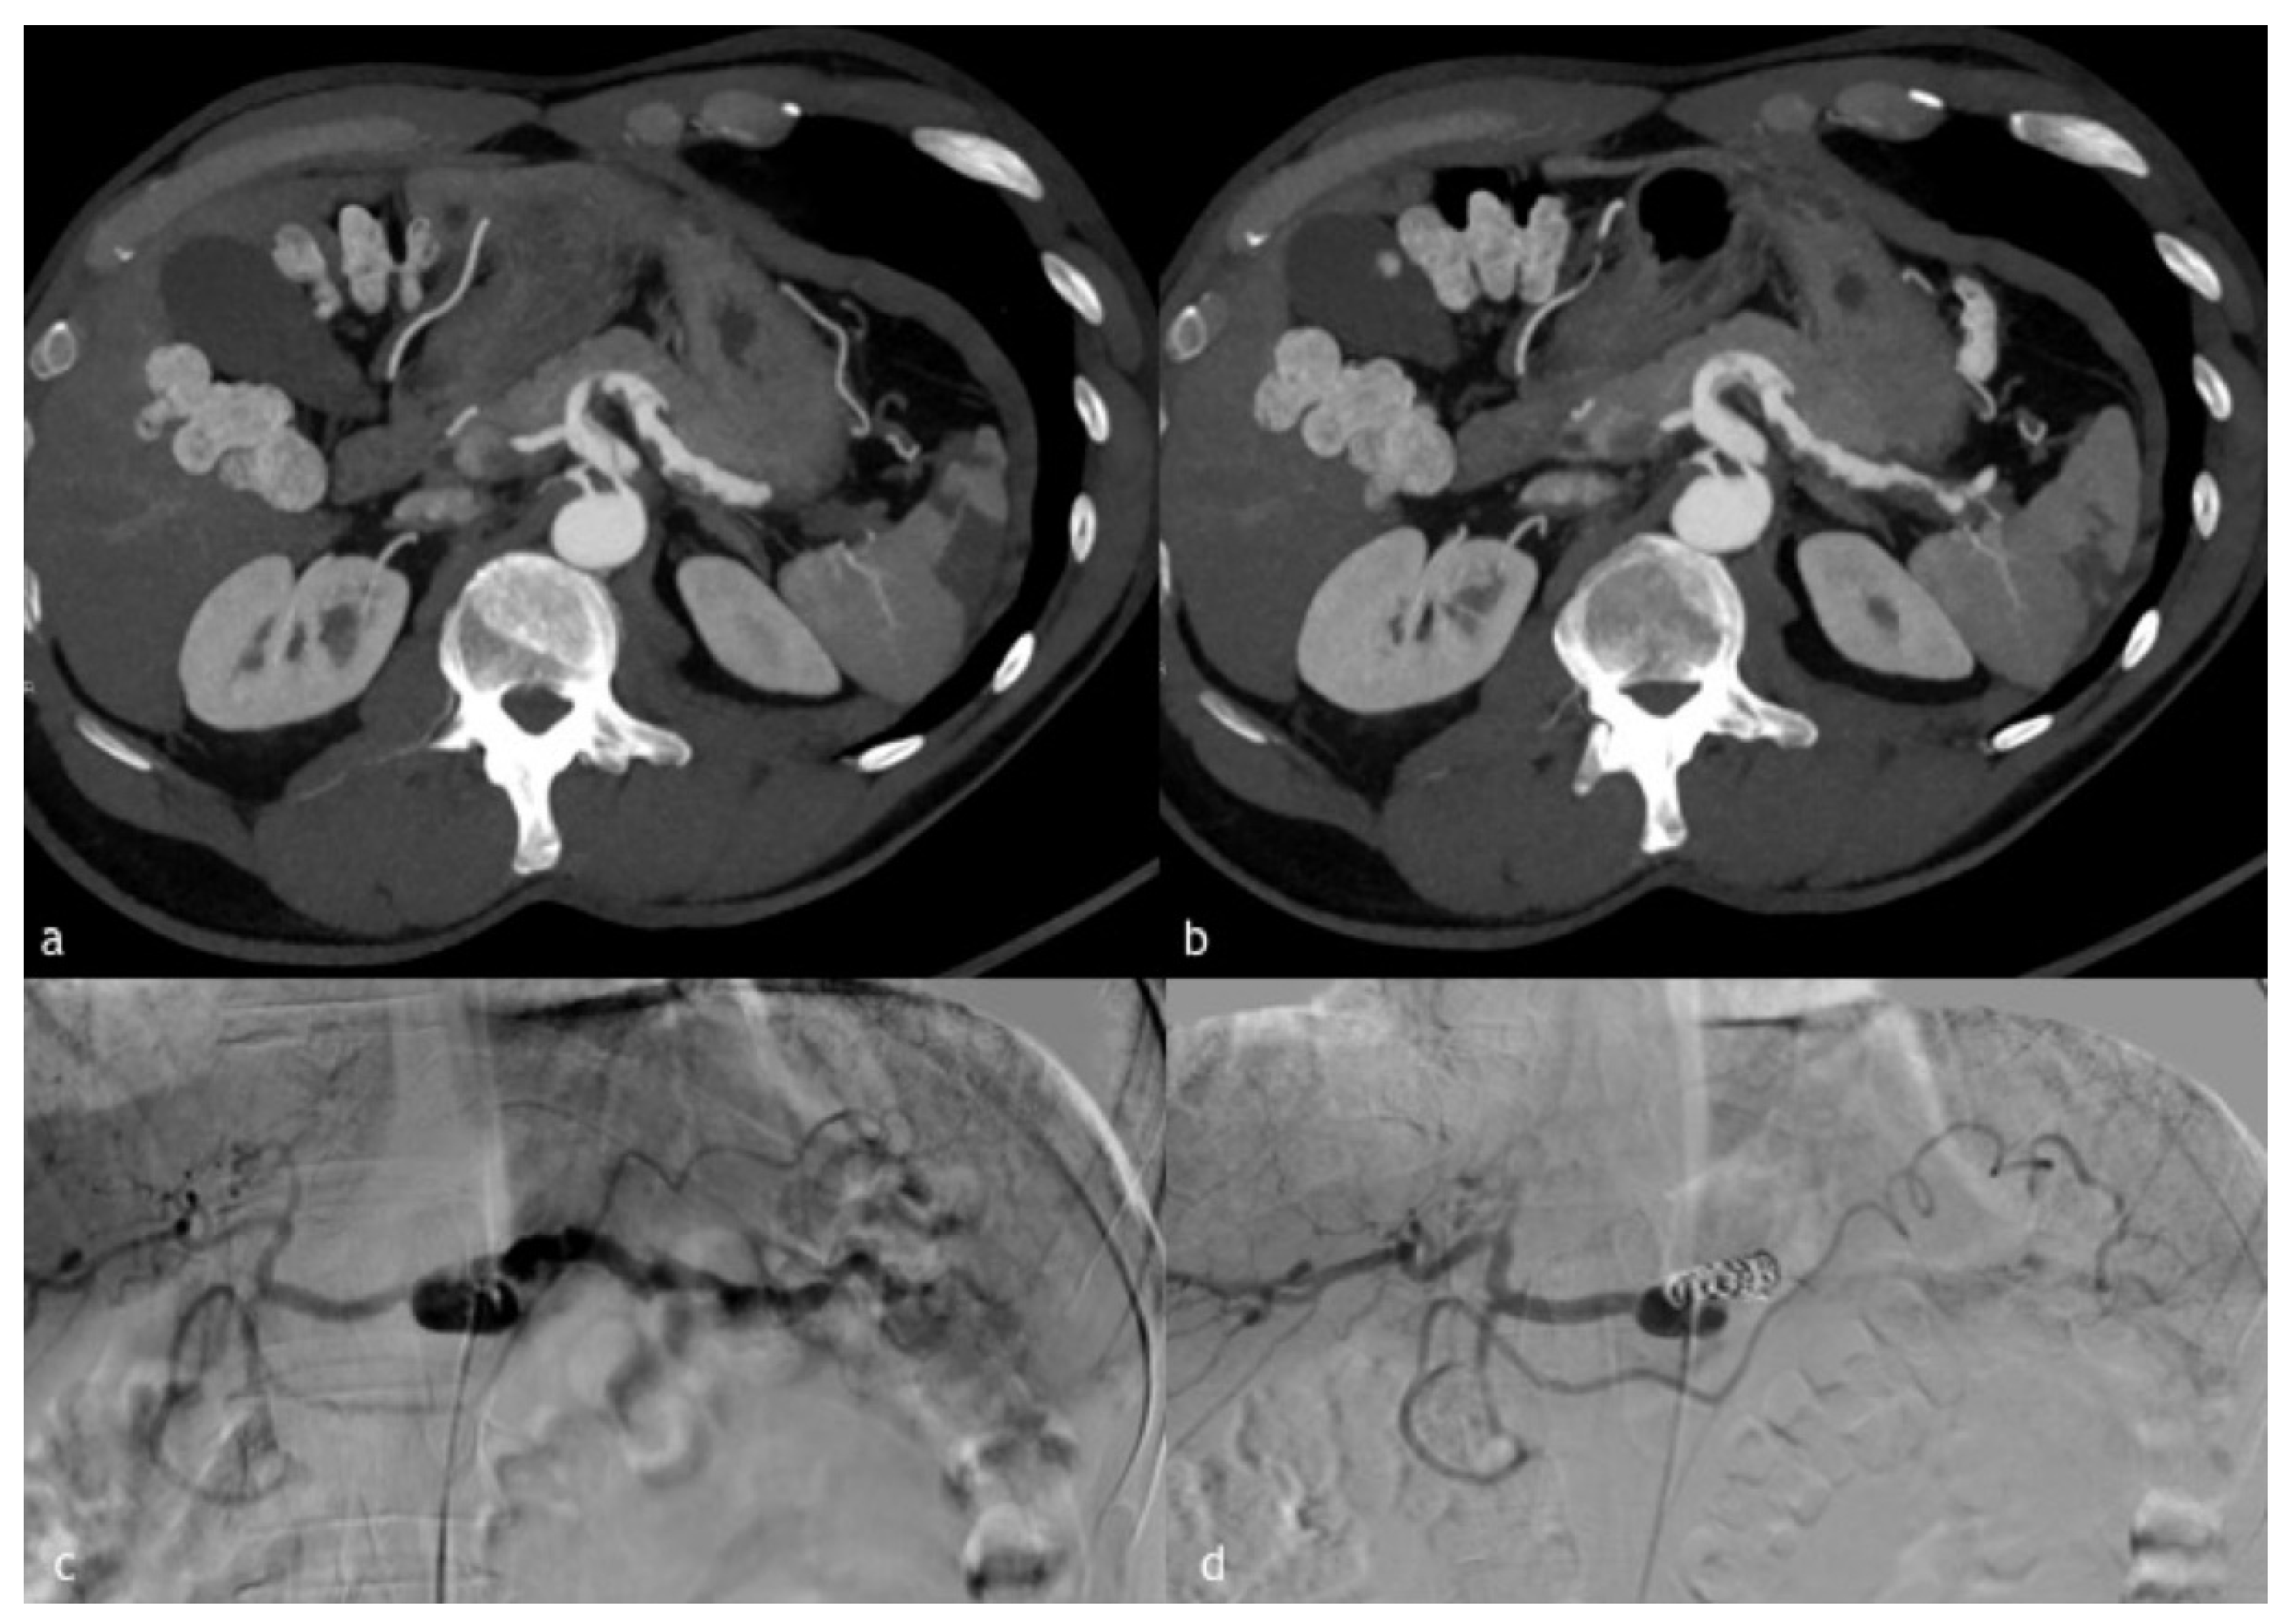

Figure 1. (ad). A 60-year-old man with a walled off necrosis after necrotizing pancreatitis. (a,b) Axial and sagittal MPR reconstruction images demonstrate splenic artery PSA (circle) in direct connection with a walled-off necrosis, previously treated surgically. (c) Angiographic images of splenic artery PSA (arrow in (c)). (d) Final angiographic control after coil embolization demonstrates splenic artery recanalization distal to coil embolization by magna pancreatic artery.